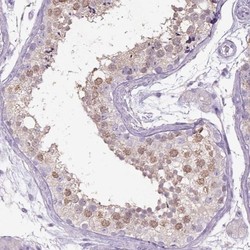

- Immunohistochemistry-Paraffin: NAALADase-2/NAALAD2 Antibody [NBP2-56951] - Immunohistochemical staining of human testis shows moderate cytoplasmic positivity in cells in seminiferous ducts.